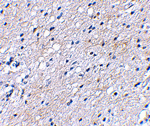

Immunohistochemical staining of human brain tissue using BAP3 antibody at 2.5 ug/mL.